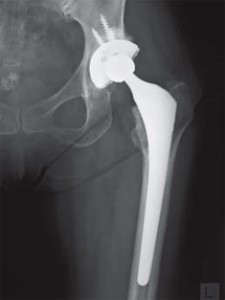

いわゆるインプラントとはどういったモノなのでしょうか?インプラントとは、医科と歯科において体内に埋め...